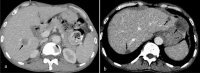

The purpose is to discuss abdominal tuberculosis mimicking malignancy involving the abdominal viscera. TB of the abdominal viscera is common, especially in countries where tuberculosis is endemic and in pockets of non-endemic countries. Diagnosis is challenging as clinical presentations are often non-specific. Tissue sampling may be necessary for definitive diagnosis. Awareness of the early and late disease imaging appearances of abdominal tuberculosis involving the viscera that can mimic malignancy can aid detecting TB, providing a differential diagnosis, assessing extent of spread, guiding biopsy, and evaluating response.